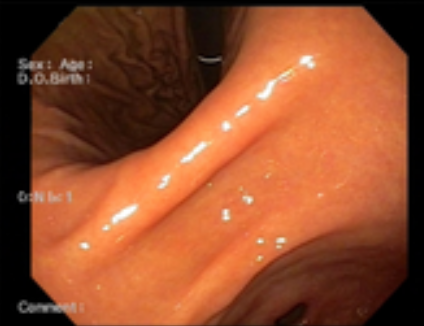

위내시경 검사는 위나 십이지장, 식도를 내시경 카메라로 살펴보는 검사로 평소 소화가 잘 되지 않거나 더부륵함, 메스꺼움, 복통, 속 쓰림, 구토 증상 등이 있다면 위염, 역류성식도염, 위용종, 위궤양, 위출혈, 십이지장질환, 위암, 식도암 등이 있을 수 있으므로 꼭 해보는 것을 권장드립니다.

위내시경 검사의 방법은 수면과 비수면으로 진행되는데 비수면 위내시경 검사의 소요 시간이 5분~10분 정도밖에 걸리지 않아 빠르고 간편합니다. 비수면 위내시경 검사의 경우 직접 본인의 위 상태를 직접 눈으로 볼 수 있어 조금 더 위 건강에 신경 쓸 수 있다는 장점이 있습니다.

위내시경 검사 중 조직검사를 통해 헬리코박터 감염 여부도 확인할 수 있습니다. 헬리코박터 파일로리 균 검사의 경우 1~2일이 지나면 결과를 알 수 있고, 조직 검사의 경우 7일에서 10일 정도 후 감염여부를 알 수 있습니다. 한 의료기관에서 위내시경 검사를 받았다면 2년 뒤에도 같은 병원에서 정기적으로 진행하는 것이 환자한테 좋습니다.